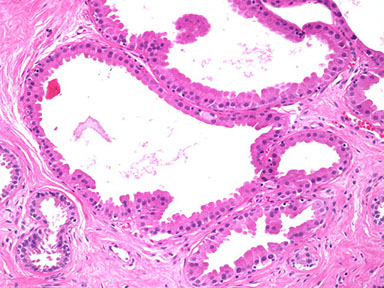

As the lactiferous duct runs deeper into the breast tissue it branches out into segmental branches which are smaller but still lined by two layers (arrow): the luminal epithelial layer of cuboidal to columnar cells and an outer myoepithelial contractile layer.

This photomicrograph depicts a sub-segmental duct (arrow) giving rise to multiple “Terminal duct lobular units (arrowheads)” embedded in dense stroma. The TDLU are terminal units of the duct system.